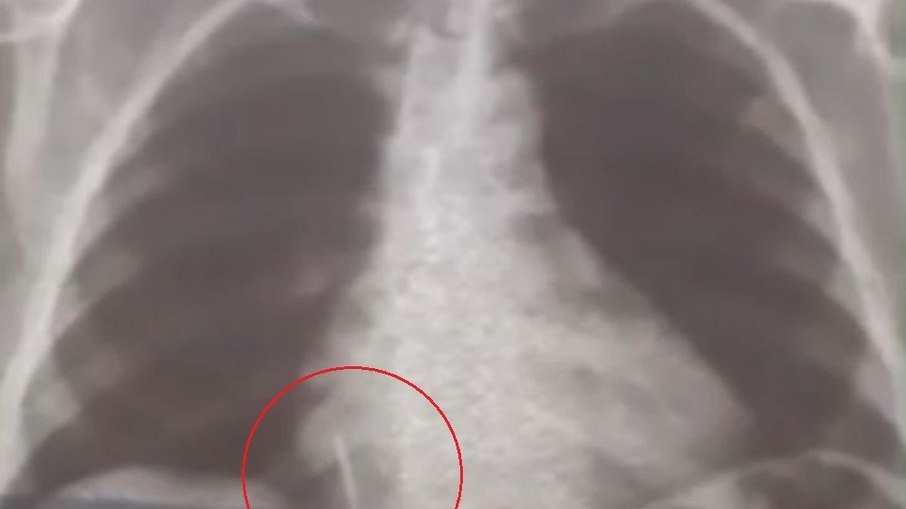

Uma mulher de 55 anos engoliu uma broca enquanto extraía um dente em uma unidade de saúde no município de Lajes, no Rio Grande do Norte . O material está alojado pulmão de Iolanda Mariano de Melo Simplício desde o último dia 26 e, de acordo com o filho da mulher, a paciente sente muitas dores e já perdeu cerca de 10 quilos.

“A Secretaria Municipal de Saúde nos deu assistência para a realização dos exames. A gente foi para Natal inúmeras vezes com ela para fazer tomografia, raio-x, hemograma, risco cirúrgico, mas até agora nada. Já são quase 29 dias e praticamente não temos resposta. A gente quer uma solução, porque é um corpo estranho que está dentro do pulmão dela”, disse Rohnhalyson Mariano, filho da mulher.